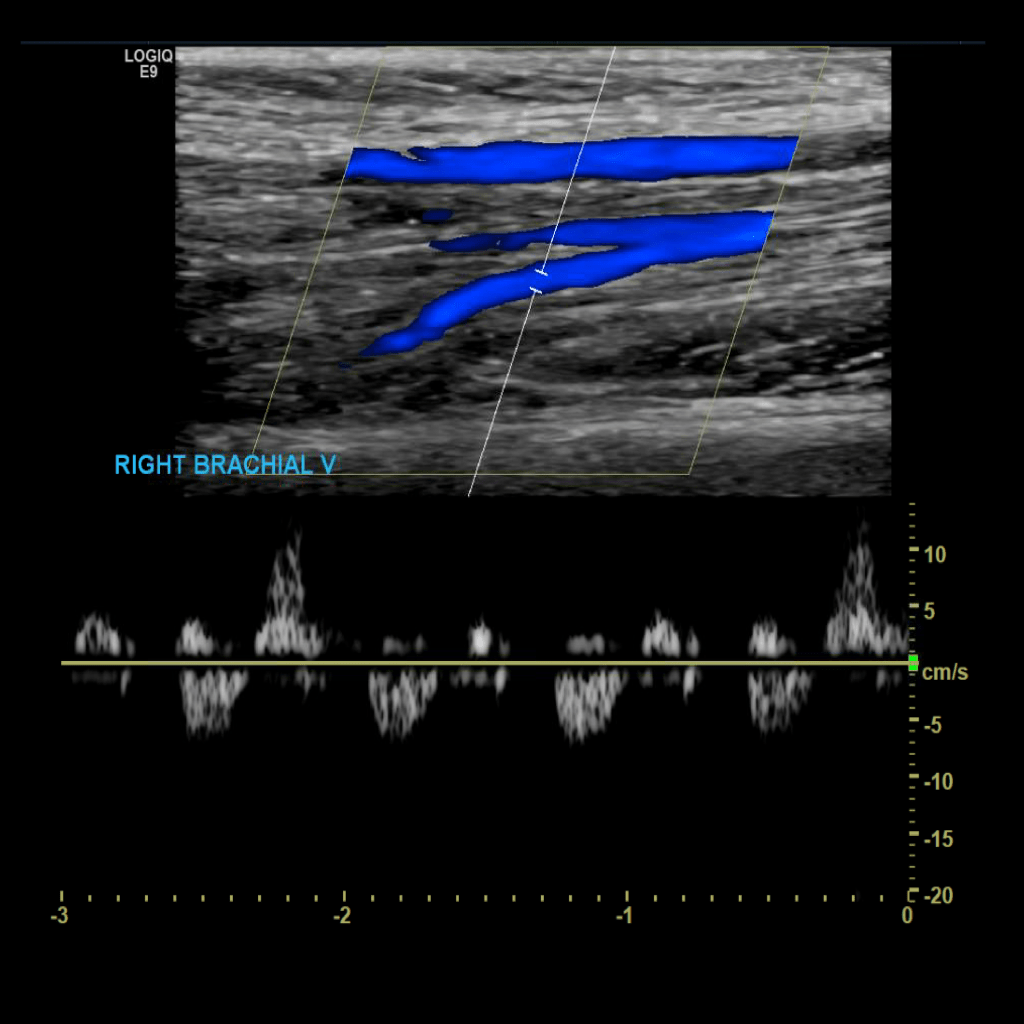

Scan the brachial veins in grey scale, compression, color doppler and spectral doppler

Brachial vein thrombosis